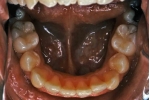

治療前後の比較